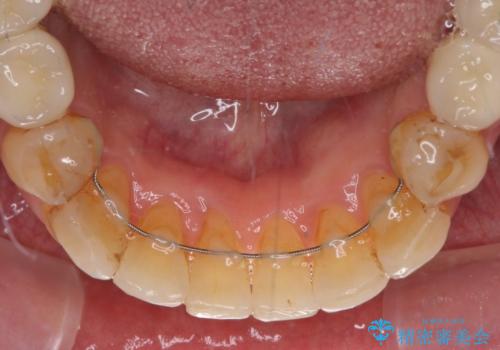

- 矯正装置

- インビザライン

矯正治療を希望して来院されましたが、歯周病を併発していたため、矯正治療開始前の処置が非常に多くなりました。特に歯槽骨の再生治療を行ったため、外科処置後の静置期間が長くなり、4年弱の治療期間となりました。

治療後には咬みやすさだけでなく、前歯が大変審美的に仕上がり、患者様には大変満足していただきました。

- 矯正治療後の保定が不十分だと後戻り(元の位置に戻ろうとする動き)をします